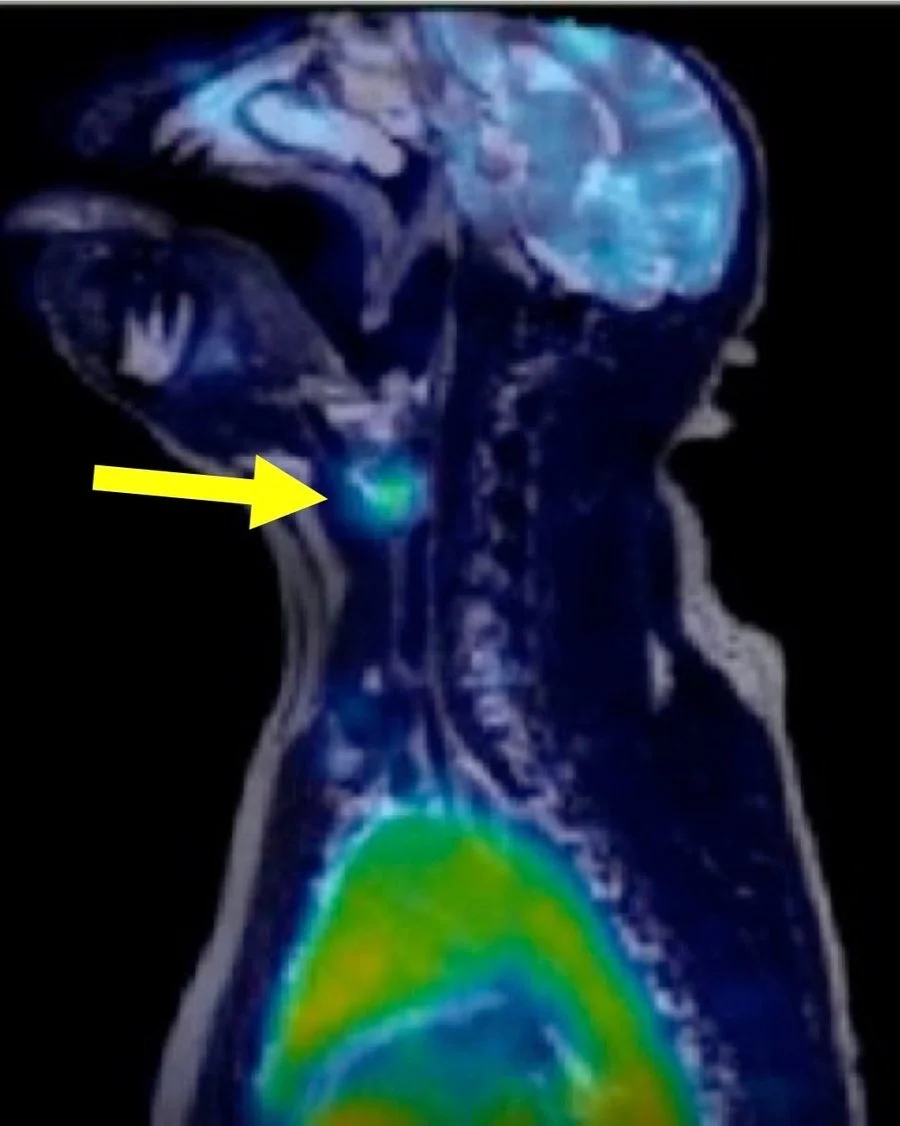

We specialize in device fabrication and contracting services geared toward applications to Positron Emission Tomography (PET) Imaging. We manufacture photoredox radiolabeling reactors, catalysts and radiolableing kits for purchase. Below are the products and services we offer.

Imaging and PET Tracer Design

We offer custom radiotracer design and imaging services for biodistribution studies.